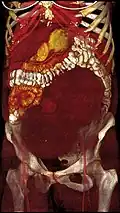

-

A very large (9 cm) fibroid of the uterus which is causing pelvic congestion syndrome as seen on CT -

Giant leiomyomas almost filling the abdomen -